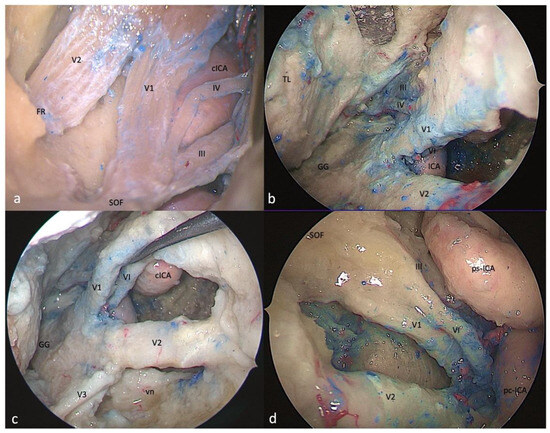

3.1. Clinoid Triangle (Dolenc’s Triangle)

3.1.1. FTOZ Perspective

3.1.2. SETOA Perspective

3.1.3. EEEA Perspective

3.2. Oculomotor Triangle (Hakuba’s Triangle)

3.2.1. FTOZ Perspective

3.2.2. SETOA Perspective

3.2.3. EEEA Perspective

3.3. Supratrochlear Triangle (Paramedian)

3.3.1. FTOZ Perspective

3.3.2. SETOA Perspective

3.3.3. EEEA Perspective

3.4. Infratrochlear Triangle (Parkinson’s triangle)

3.4.1. FTOZ Perspective

3.4.2. SETOA Perspective

3.4.3. EEEA Perspective